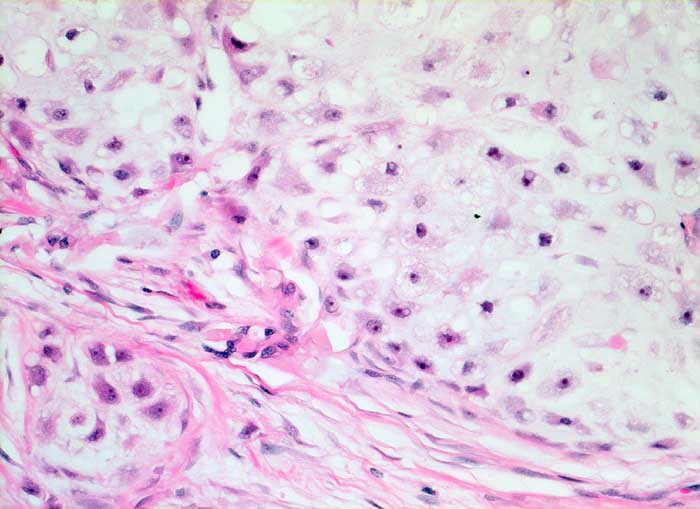

Chondrosarkom

Das Sarkom ist deutlich zellreicher als normaler Knorpel und die Tumorzellen sind deutlich vergrössert, aber noch gut als Knorpelzellen erkennbar.

Makroskopischer Befund des Thoraxwandteilresektates: halbkugeliger Tumor (7,5x7x3,6cm). Auf Schnitt findet sich ein gallertiger, teils knorpeliger Tumor mit Nekrosen und Einblutungen. Tumor durch die beiden mittleren Rippen durchtretend.

Brustwandtumor parasternal rechts Teils extra-, vorwiegend intrathorakal